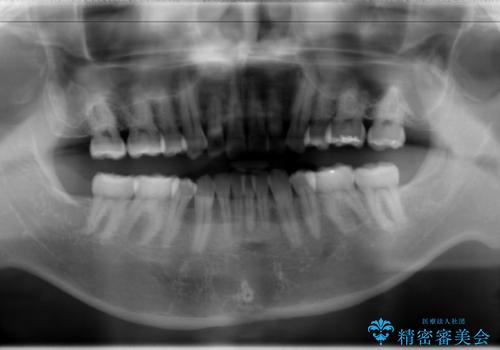

- 以前、上下左右4本抜いてワイヤー矯正をしていた方で、後戻りで下の前歯のガタガタを気にして来院されました。

マウスピース矯正にて、下の歯はIPR(歯と歯の間を削る)を入れることでガタガタの改善、咬み合わせの深さも改善をはかる治療計画をたてました。

歯と歯の間を削って隙間を作って矯正をしています。

保定装置(後戻り防止のための装置)は、基本的にはマウスピースタイプをお渡ししているのですが、患者様のご希望で取り外ししないタイプを希望されたので、前歯の裏側を細いワイヤーで固定(ボンディングリテーナー)を作成しています。